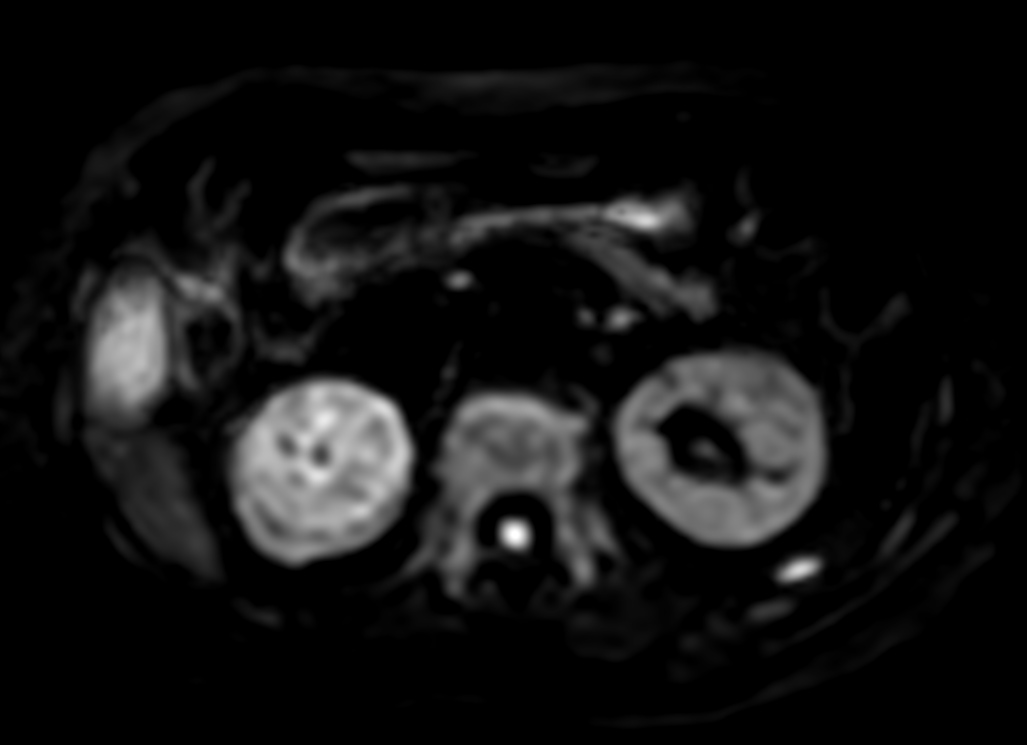

Patient with a kidney lesion. The ExamCard includes techniques for 3D imaging (PelvisVIEW, eTHRIVE) allowing for multiple image directions in one single scan, efficient fat-free imaging over large field-of-views (mDIXON XD), a multi-phase contrast-enhanced sequence (4D FreeBreathing) to improve imaging confidence and Compressed SENSE to accelerate the entire exam.

DWI b800